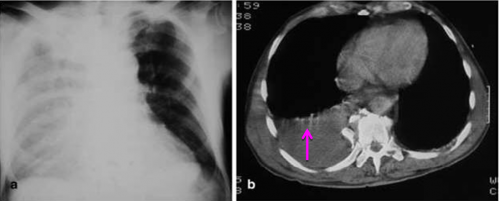

מבחינה קלינית חזה-דם מאופיין על-ידי החלשת קולות הנשימה, ועמימות בניקוש. בצילום חזה ניתן לראות עכירות המופיעה תחילה בבסיס הריאה ואחר כך גוברת והולכת. בשכיבה העכירות מתפשטת על פני כל הריאה, ובישיבה ניתן לראות פלס נוזל בחלק התחתון של הריאה (תמונה 10.16). ממצאים אלה נראים בבירור ב-CT חזה (תצלום 11.16).